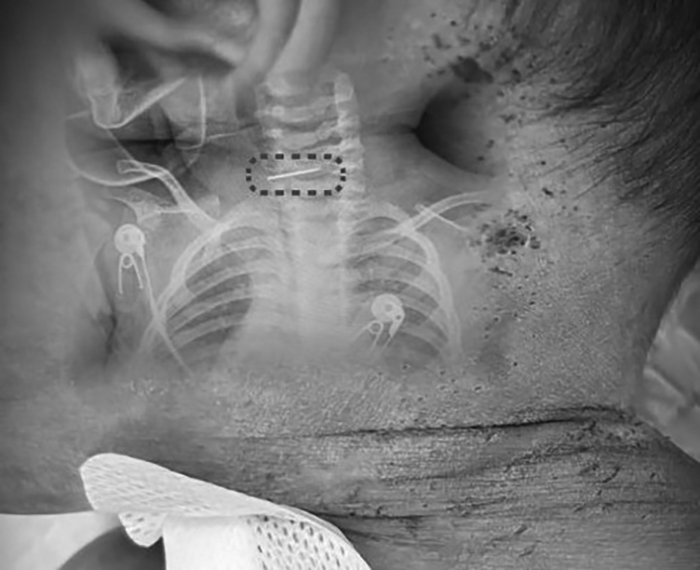

The 10-month-old boy with many needle marks across his body. Photo: Red Star News |

Doctor Sui Wenyuan of the Spine Center, Xinhua Hospital, Shanghai Jiao Tong University School of Medicine, admitted the patient with a high fever. Examinations revealed 500 to 600 scabbed needle marks covering the child's head, torso, and limbs.

Crucially, doctors discovered a broken shoe-sewing needle lodged deep in the child's cervical spine. An emergency surgical team immediately operated to remove the foreign object. Doctor Sui noted this operation was exceptionally complex, as a 10-month-old's cervical spine is undeveloped and fragile, presenting risks significantly higher than for adults.

"Shoe-sewing needles often have barbs at the tip. If removed incorrectly, they can hook into soft tissues, causing extensive damage. Furthermore, the needle's end was close to the carotid artery; a small mistake could lead to the child's death on the operating table," doctor Sui shared on Douyin.